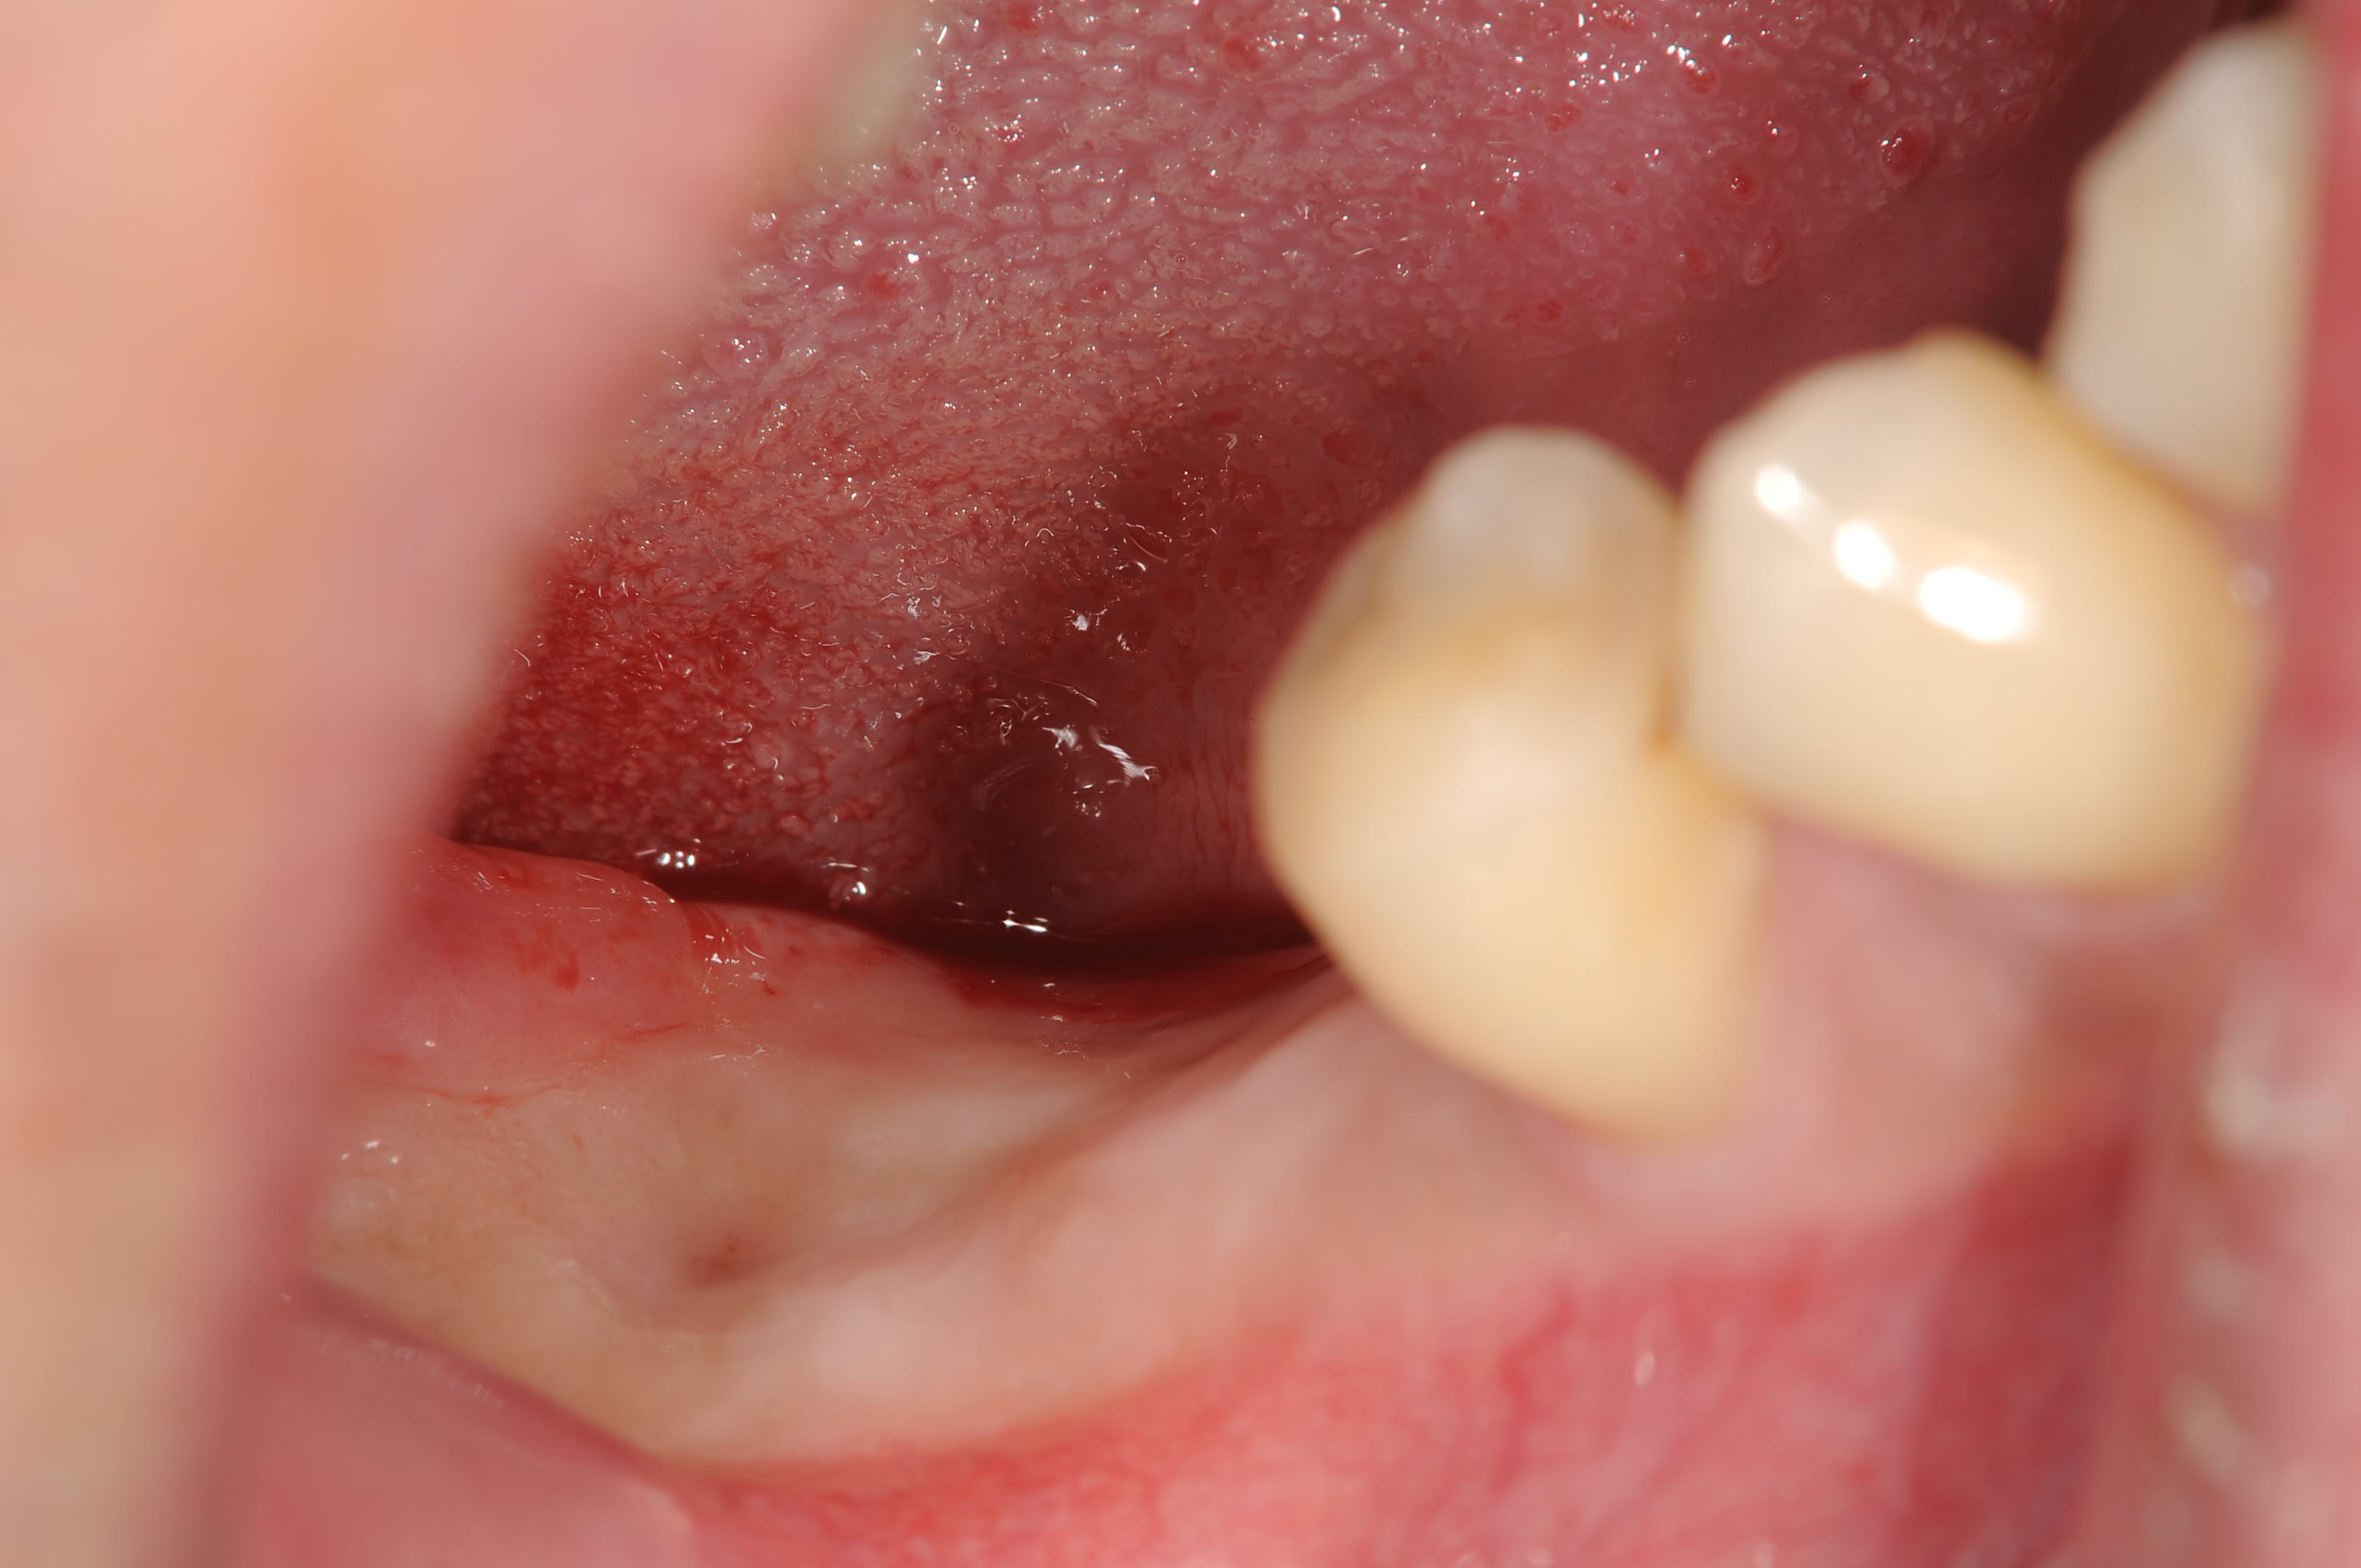

昨日のオペでしたが、右下6番部位にサイブロンインプラントのワイドネック11mmを埋入しました。

抜歯窩でもなく、骨幅深さともに問題なく、通常に骨縁埋入の1回法で終了しました。

付着歯肉の幅もそこそこあります。

骨縁埋入でプラットフォームスイッチのヒーリングアバットメント装着しました。